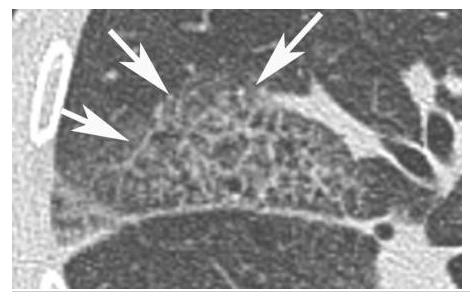

Sarcoïdose.

Présence de micronodules dans la région moyenne des poumons, situés en région sous-pleurale, le long des septa interlobulaires (flèches) et le long des bronches (têtes de flèches).